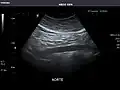

It can be used on the abdominal aorta to detect or exclude abdominal aortic aneurysm. For this purpose, the standard aortic measurement for abdominal aortic aneurysm is between the outer margins of the aortic wall.[4]

Aorta: Visualized portions normal in caliber, 16 x 15 mm.

Aorta -